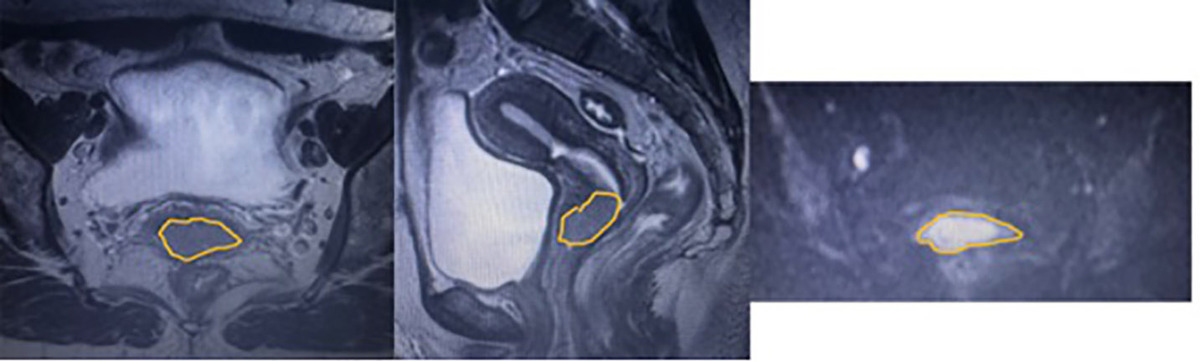

This retrospective study included 88 women (mean age, 51.1 ±13.0 years; range, 25-83 years) with histopathologically confirmed cervical cancer (47 SCC, 41 non-SCC). For each patient, axial and sagittal T2-weighted imaging (T2WI) and diffusion-weighted imaging (DWI) were available, along with clinical metadata. Radiomic features (shape, first-order, and texture features including gray-level co-occurrence matrix, gray-level run length matrix, and gray-level size zone matrix) were extracted from each sequence, yielding 945 features per patient. A feature set was created by combining features from all three sequences. The least absolute shrinkage and selection operator (LASSO) method was used for feature selection. Three supervised classifiers – random forest (RF), support vector machine (SVM), and logistic regression (LR) – were trained to classify SCC versus non-SCC.